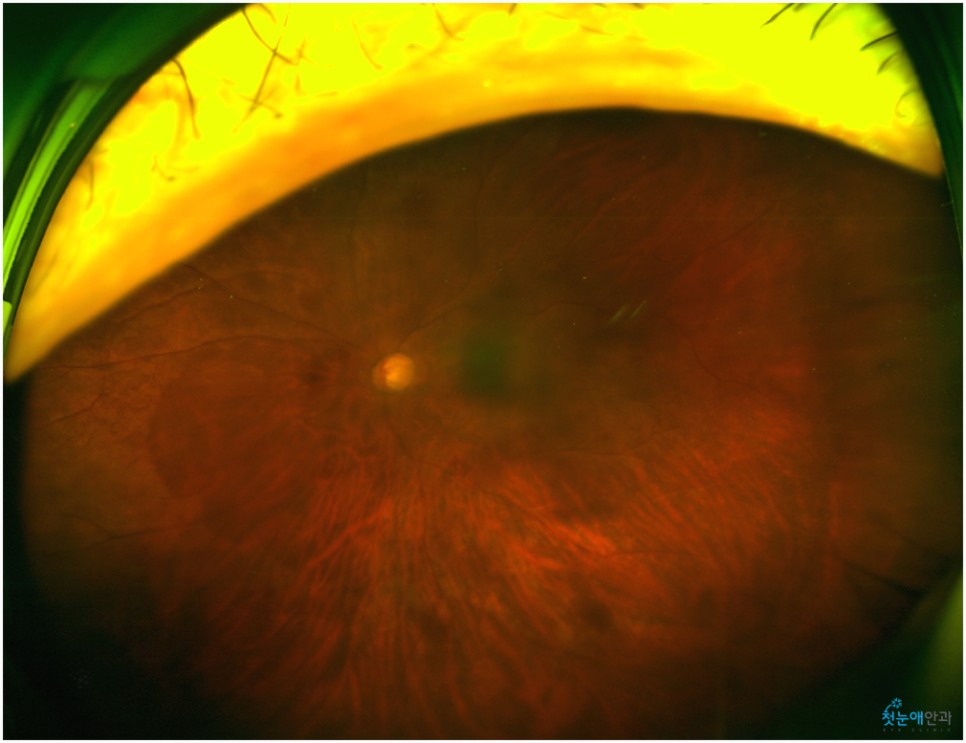

백내장이 상당히 진행되면 수정체가 흐려져 눈 아래의 망막 관찰이 어렵습니다.때문에 사진을 찍어 검사해봐야 하는데 위와 같이 흐릿한 사진이 찍혀 사실상 망막 관찰이 어렵습니다.뿐만 아니라 심한 백내장은 부분마취 수술 진행이 어려워 안구마취나 전신마취로 수술하거나 종합병원으로 전환해 수술해야 합니다.뿌옇게 변했는데도 그냥 놔두면 위 사진처럼 더 심해져 시력이 저하되는 상황까지 이어지게 됩니다.